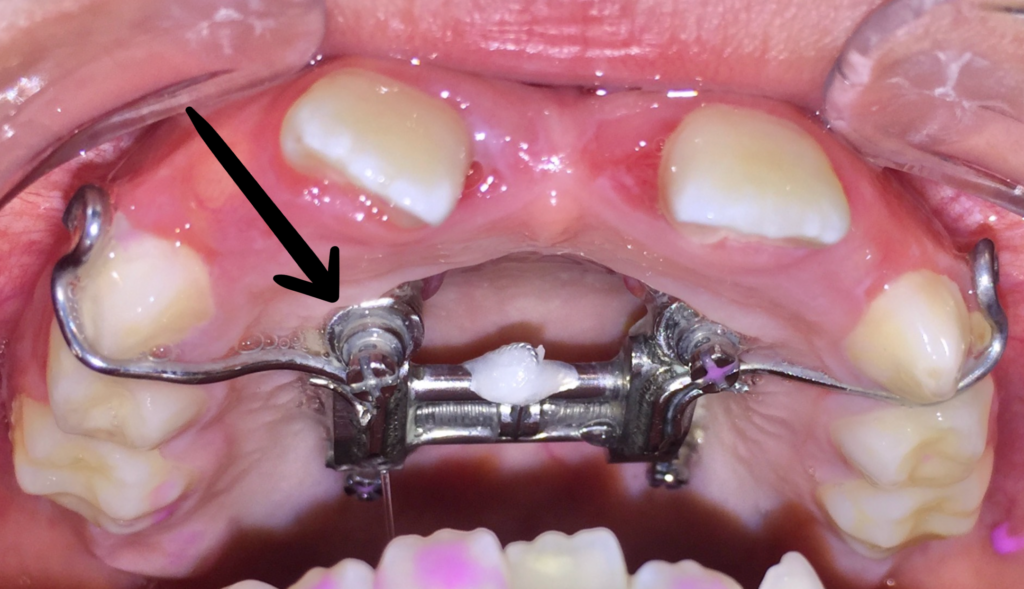

9. Microcargol afluixat, amb moviment o inflamació

En els tractaments amb aparells amb suport ossi, els cargols poden perdre força degut a restes de menjar que provoquen inflamació.

Si es dóna el cas, realitzeu els passos següents:

1. Contacteu amb la clínica Boca a Boca i agafeu hora amb la Dra. Villa. Els cargols són un tema quirúrgic i la Dra. Cubells no us pot ajudar en aquest sentit.

2. Higiene molt exhaustiva de la zona, especialment amb el fil dental i/o els raspallets interdentals. (Podeu mullar el fil o el raspallet amb clorhexidina).* Instruccions d’higiene

3. Apliqueu Gel de clorhexidina la llaga, després de cada raspallat i a demanda entre raspallats si cal.* (Producte complementari a les instruccions d’higiene; ells sols NO solucionaran la inflamació).

Microcargol anclat

Microcargol afluixat